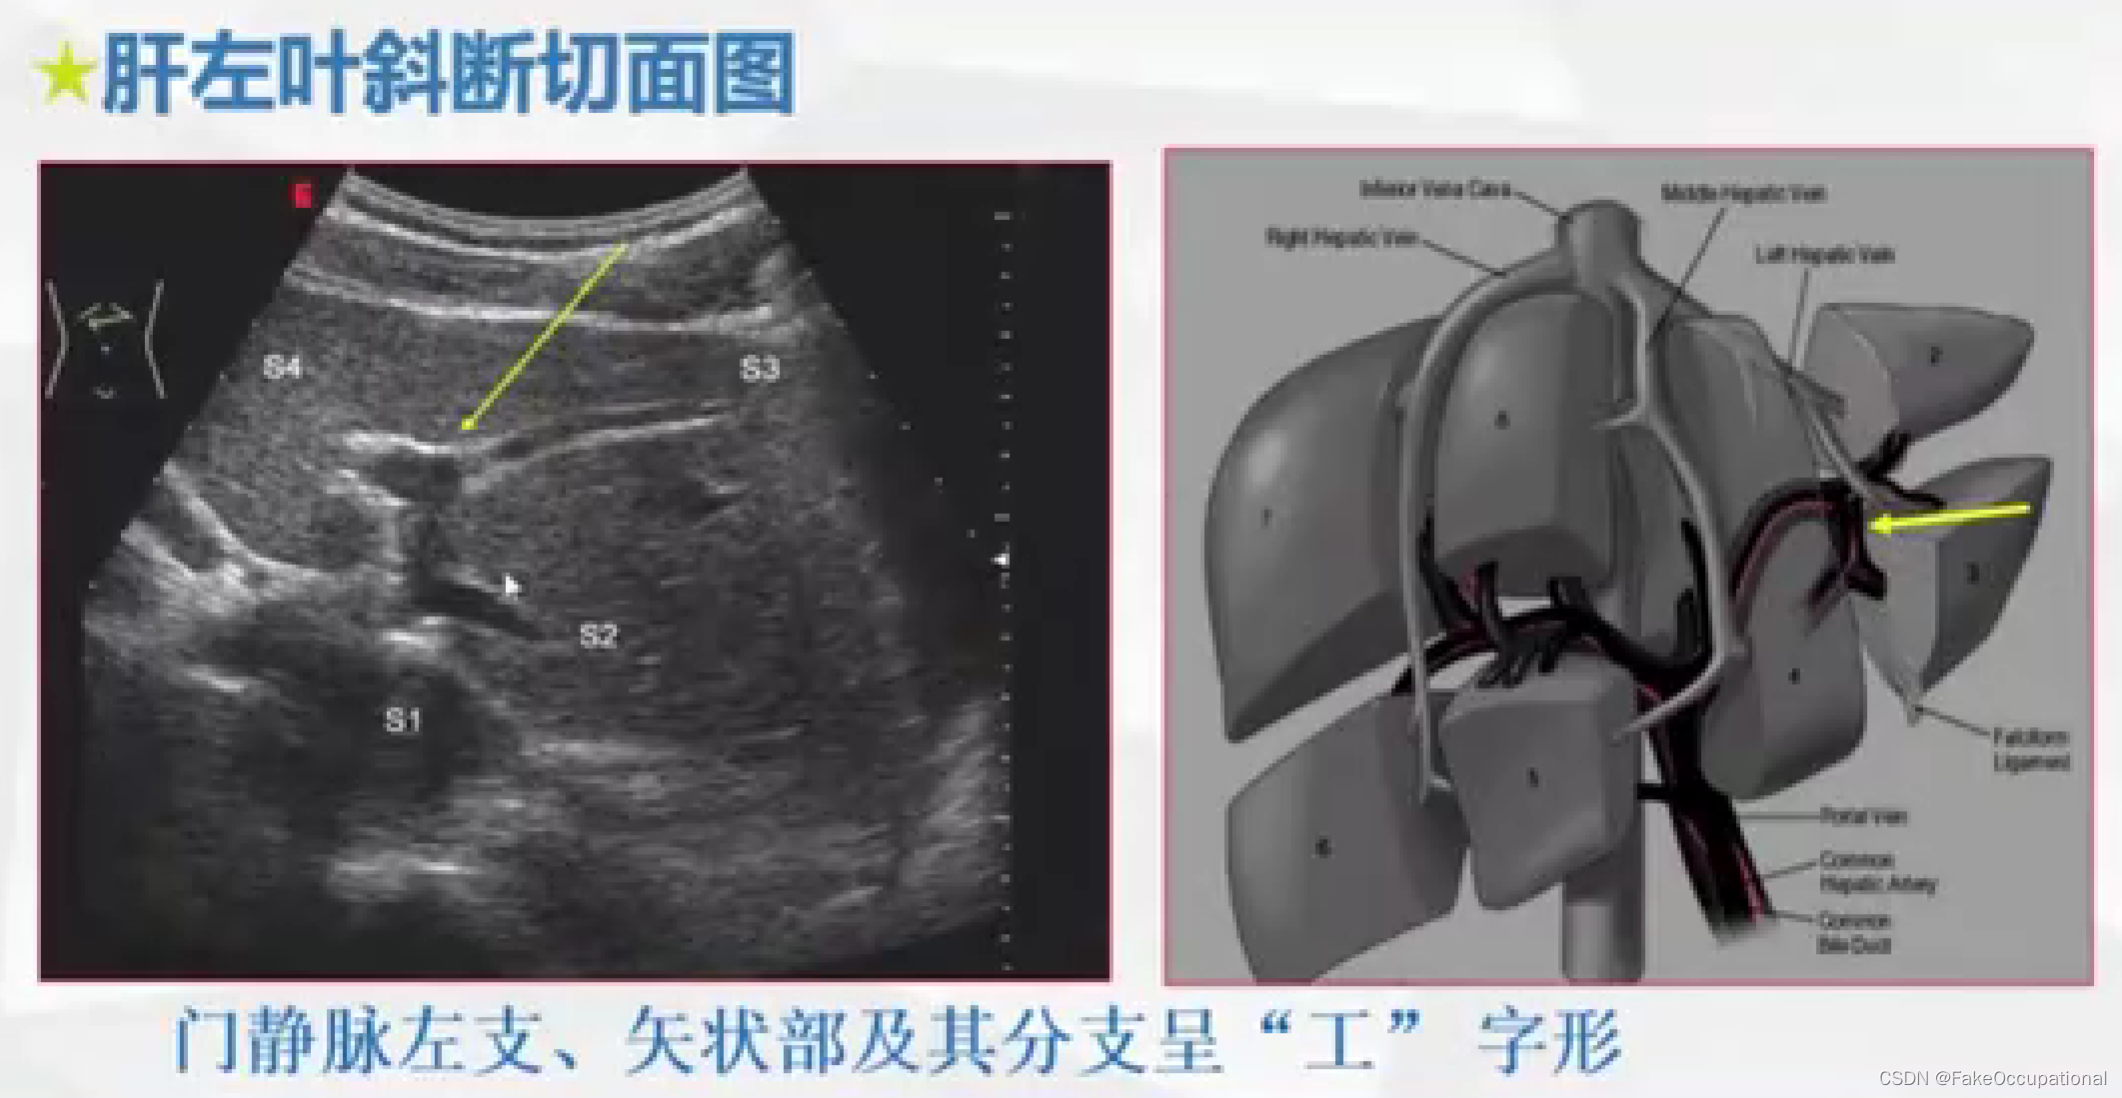

肝脏解剖概要

肝脏超声检查技术